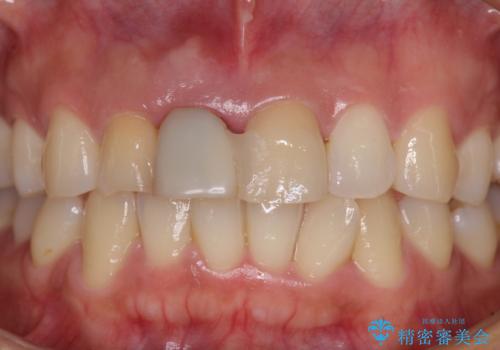

- 仮歯のまま前歯を放置しているとのことで来院された患者様です。

目視で確認できるほどしっかりとした破折が認められ、抜歯が必要と判断されました。

抜歯後は歯肉が痩せてしまうため、歯肉移植を行って歯肉の形態を改善した後、オールセラミックブリッジにて補綴することとしました。